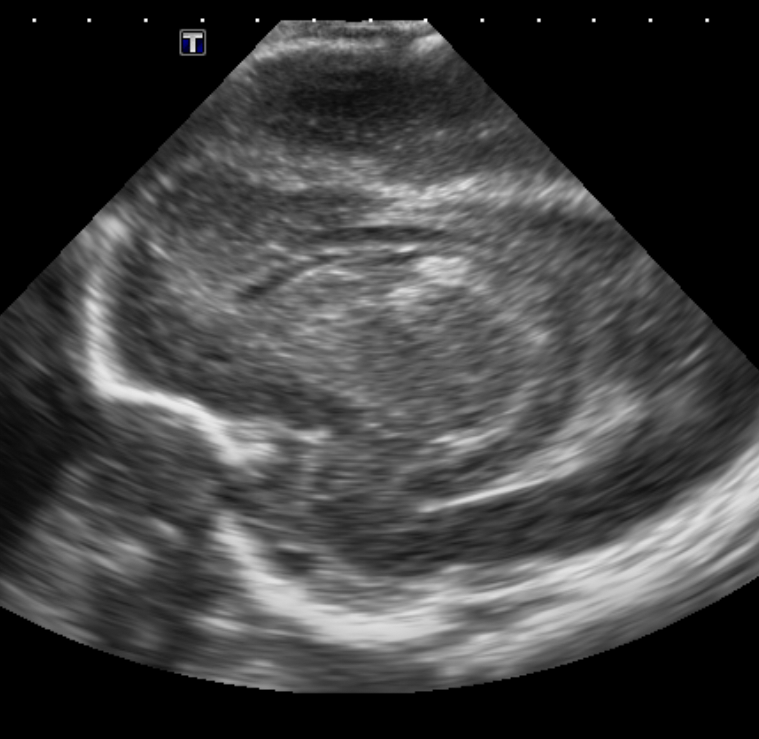

Info Images Findings Impression Reco/Acuity Case Images View Images / Launch Visage Case Notes History Full term infant. We are asked to evaluate posterior fossa cyst. Exam Gray scale and Doppler Ultrasonographic examination of the head. Prior Study N/A Dicom View Reference Material

Section 1 Submit Findings Case149 Findings Brain The brain is immature. Yes No There is under-sulcation and open sylvian fissures. Yes No There is/are multiple hypoechoic areas in the periventricular white matter. Yes No There is/are multiple hyperechoic areas in the periventricular white matter. Yes No There is diffuse cerebral edema with diffusely increased echogenicity of the brain parenchyma and loss of grey white matter differentiation. Yes No The thalami/basal ganglia are hypoechoic. Yes No There is periventricular calcification. Yes No There is intra-parenchymal calcification. Yes No CSF spaces/ventricular system There is a prominence of the extra axial fluid spaces. Yes No There are debris/septations in the extra axial fluid spaces. Yes No There are debris/septations in the ventricles. Yes No There is a subdural collection on the right/left side. Yes No There is prominence of the ventricular system. Yes No There is an asymmetry of the ventricular system. Yes No There is a cavum septum pellucidum. Yes No There is a midline shift towards right/left. Yes No The choroid plexus is bulky/lobulated. Yes No There is a choroid plexus cyst measuring… Yes No There are debris/clots in the occipital horn. Yes No There is a posterior fossa cyst measuring… Yes No The tentorium is elevated/depressed. Yes No The lateral ventricle/s are dilated. Yes No The third ventricle is dilated. Yes No The 4th ventricle is dilated. Yes No There are pseudo cysts. Yes No Germinal matrix hemorrhage (Only in the premature infants): Please do not answer if the patient is a full term. There is a germinal matrix hemorrhage, consistent with a grade I hemorrhage. Yes No There is an intraventricular extension consistent with a grade II hemorrhage. Yes No There is an intraventricular extension with the dilatation of ventricles, consistent with a grade III hemorrhage. Yes No There is an intra-parenchymal extension, consistent with grade IV hemorrhage. Yes No On color Doppler examination, the Resistive index in the anterior cerebral artery is… There is a loss of the diastolic flow on the Doppler exam. Yes No There is altered vascularity on Doppler imaging. Yes No There is an AVM in the region of… Yes No